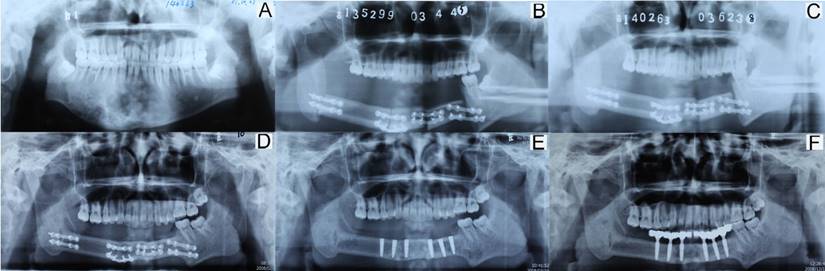

Reconstruction

In total, twenty-three patients underwent reconstruction with free tissue graft. Sixteen cases were reconstructed with fibula flap graft, four cases with anterolateral thigh flap graft, two cases with iliac flap graft, and one with free rib graft. One anterolateral thigh flap graft of a 6-year-old boy was removed due to vascular crisis. The youngest patients among those with successful reconstruction with different flaps were aged 1 year, 7 years, 10 years, and 13 years. The total success rate was 96% (22/23). For patients, recovering the oral function is important and necessary after operation. In our cases series, both the removable prosthesis and fixed prosthesis (implant) were common methods. Sometimes, the implantation could get absolutely results. In Figure 3, a 17-year-old boy diagnosed of ossifying fibroma underwent segmental resection of mandible. The defect was reconstructed by a fibula flap grafting. Bony union was observed three months after operation. Five years after operation, implantation was applied and a good functional outcome was achieved.

Figure 3

Imaging of reconstruction with a fibular flap graft in a 17-year-old boy. (A: pre-operation; B: one week after operation; C: three months after operation; D: five years after operation, pre-implantation; E: implant placement; F: implant-support prosthesis).